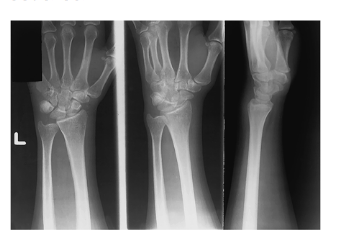

Exceptions to Positioning Rules

Postreduction upper and lower limbs ( Ex: Wrist in a cast usually three views but it’s fractured. Only 2 views (PA and lateral ) to check alignment.

Joints in a prime interest area how many projections?

Three

AP or PA

Lateral

Oblique